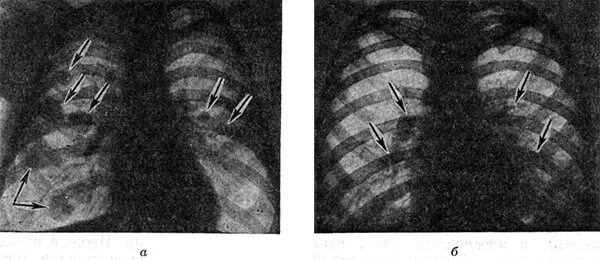

Рмж метастазы в легкие